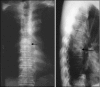

Pyogenic spondylitis

Pyogenic spondylitis is a neurological and life threatening condition. It encompasses a broad range of clinical entities, including pyogenic spondylodiscitis, septic discitis, vertebral osteomyelitis, and epidural abscess. The incidence though low appears to be on the rise. The diagnosis is based on clinical, radiological, blood and tissue cultures and histopathological findings. Most of the cases can be treated non-operatively. Surgical treatment is required in 10-20% of patients. Anterior decompression, debridement and fusion are generally recommended and instrumentation is acceptable after good surgical debridement with postoperative antibiotic cover.